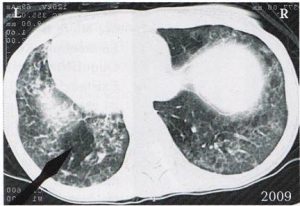

Fia halálakor a „halálfélelem-konfliktus” miatt az anyánál elindult egy szoliter tüdőhólyagocska sejtszaporulat. Az ezt követő tüdőtuberkulózist 4 évvel később diagnosztizálták.

Tisztán látszik a (sötét) kaverna. A hozzá tartozó tumor 4 éven keresztül növekedett (1996-2000). Miután éjszakánként a páciens immáron 2 éve rendszeresen verejtékezik és köhög, felfedezték nála a tuberkulózist és kezelték. Itt látható bal oldalt annak maradványa.

A bal oldali Hameri góc a ponsban a bal tüdőlebenyhez tartozik (most már kaverna, ezt megelőzően szoliter tüdőhólyagocska sejtszaporulat volt).